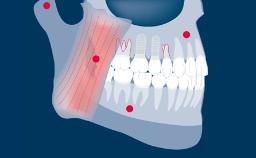

Dr. Gallucci is the Chair of the Department of Restorative and Biomaterial Siences at Harvard School of Dental Medicine. ITI Fellow since 2004, Chair of the ITI Scholarship Center at Harvard.

ITI Study Club UIC Chicago - Lecture with Dr. German Gallucci - “Implant-Prosthodontic Integration in the Esthetic Area”